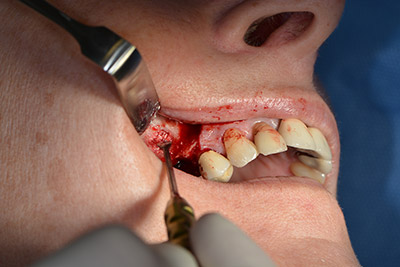

En el siguiente paso se efectúa la elevación del suelo del seno maxilar, a la vez que se coloca el implante. Para la fenestración lateral de la pared del seno maxilar Implantmed también cuenta con un ajuste predefinido en la primera posición.

La ventana se crea a una velocidad de 35.000 rpm y, a continuación, la membrana de Schneider se prepara en sentido craneal (figuras 13 a 14).

Acto seguido, se coloca el implante y se estructura el hueso. Dado el tamaño del aumento, en el caso que nos ocupa se utilizó hueso autógeno, que había surgido como virutas de fresado en el implante 16 y en la fenestración 14 y se había recogido con un colector óseo, y se combinó con material de reemplazo óseo.